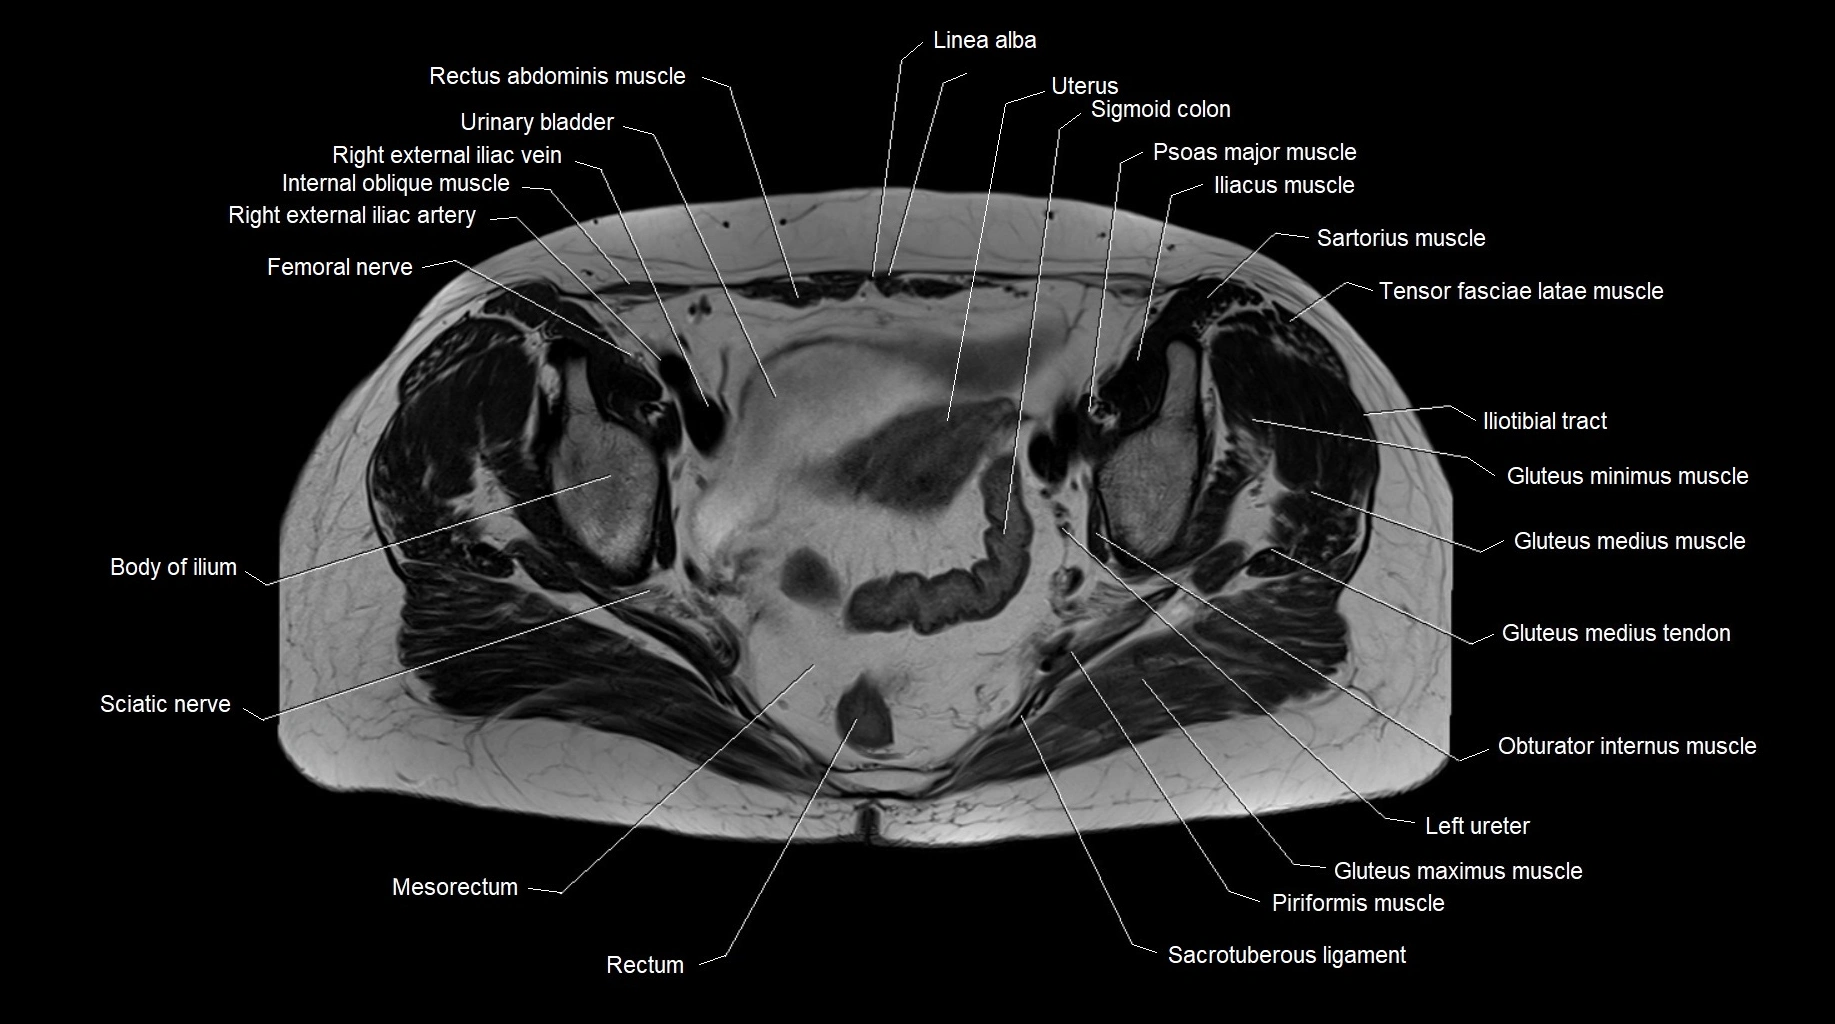

MRI images